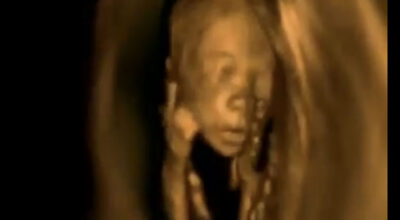

Después de haber visto en ecografías 3D cómo son los movimientos del feto, incluso las pataditas que a veces son demasiado fuertes y provocan pequeños bultitos en la tripa de las mamás. Ahora hemos sido testigos una vez más de las impresionantes imágenes de un feto pero esta vez campando a sus anchas en el vientre de su madre.

De forma nítida en el vídeo que te mostramos a continuación podrás ver cuáles son los movimientos que suelen hacer los fetos dentro de la tripa de la madre así como sus posturas más comunes y por decirlo de alguna manera, cómo es su vida ahí dentro durante los 9 meses que tienen que estar allí.

Somos capaces de distinguir su carita, nariz, manos, brazos… Incluso vemos cómo el cordón umbilical que le une a la madre se ve claramente rodeándole. ¿No te parece algo impresionante? ¡Aquí tienes el vídeo para que puedas verlo con tus propios ojos!